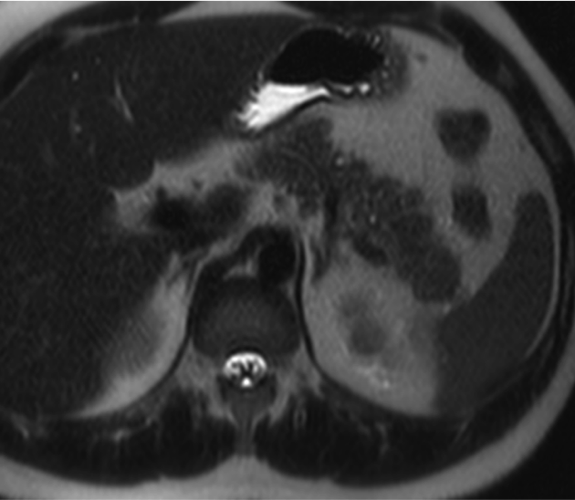

Hombre de 39 años con antecedente de fibrosis retroperitoneal.

Se solicita TC porque en RM externa realizada para control de la fibrosis retroperitoneal se informa de sospecha de neoplasia de cola de páncreas.

3. ¿Cuál es tu diagnóstico?

- A. Tumor pseudopapilar sólido pancreático con metástasis renales izquierdas.

- B. Linfoma pancreático -forma localizada- y lesiones atróficas renales izquierdas secundarias a fibrosis retroperitoneal.

- C. Lesión metastásica en páncreas de tumor primario renal.

- D. Pancreatitis autoinmune en contexto de enfermedad relacionada con la IgG4.

- E. Sarcoidosis con afectación pancreática y renal.